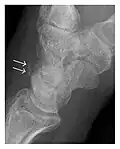

Triquetral fracture usually occurs on the dorsal aspect by impingement from the ulnar styloid or avulsion of strong ligamentous attachment. The dorsal avulsion fracture or "chip fracture" appears as a small bony fragment on the dorsal aspect of the triquetrum and is best detected on the lateral view(Figure 4). When radiography is negative in patients with high suspicion of a fracture, both MRI and MDCT will be of value. However, it has been shown that MRI is superior for detecting trabecular fractures in carpal bones.

Figure 4: Dorsal triquetral fracture of the left wrist in a 30-year-old man after a trauma. (a) Anteroposterior radiograph shows a normal appearance. (b) Lateral radiograph of the same wrist demonstrates a chip fracture off the dorsal aspect of the triquetrum (arrow).[1]